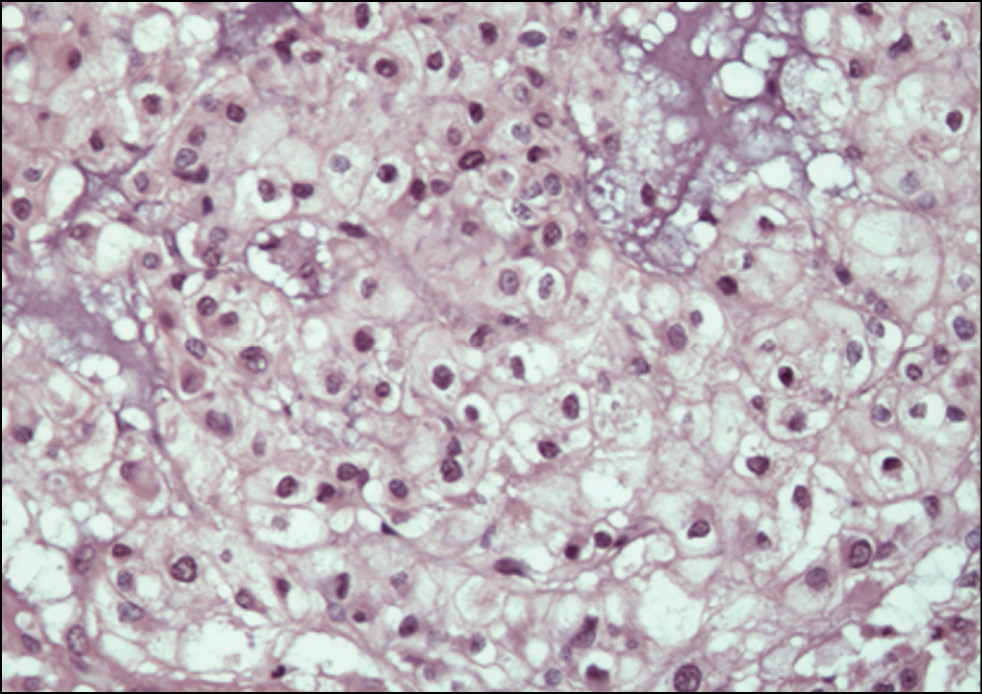

Histological examination of the surgical material revealed a solid neoplasm composed of strands or nests of epithelioid-type cells located in the mucoid intercellular matrix. The pathologic tissue was divided into lobules of different configurations and sizes by connective tissue layers. The tumor cells had large, rounded nuclei with moderate atypia and prominent nuclei. The cytoplasm was abundant and pale, with numerous cytoplasmic vacuoles, also known as physaliform cells (Fig. 10). In addition, epithelium-like cells with dense eosinophilic cytoplasm and weakly expressed vacuolization were found (Fig. 11). The cell population was predominantly mononuclear but also included binuclear and multinuclear cells, as well as cells with a ring-shaped vacuolized cytoplasm with the nucleus displaced to the cell membrane. Mitotic activity was low, and single atypical mitoses were detected. The tumor exhibited densely arranged syncytium-forming cells with a poorly expressed intercellular mucoid matrix in some areas, whereas other areas showed a predominance of the latter with only a few tumor cell islets. In addition, numerous necroses and hemorrhages were observed throughout the tumor.

Fig. 10. Micrograph. Conventional chordoma with characteristic physaliform cells with pronounced vacuolization of the light cytoplasm. Hematoxylin and eosin staining. ×400.

Fig. 11. Micrograph. Conventional chordoma. An area of densely packed epithelial-like cells with mild vacuolation and eosinophilic cytoplasm. Hematoxylin and eosin staining. ×400.

Thus, the histological picture is consistent with that of a conventional chordoma. The pathomorphologist reported that the resection margin was free of tumor (R0), confirming the surgery’s radicality.